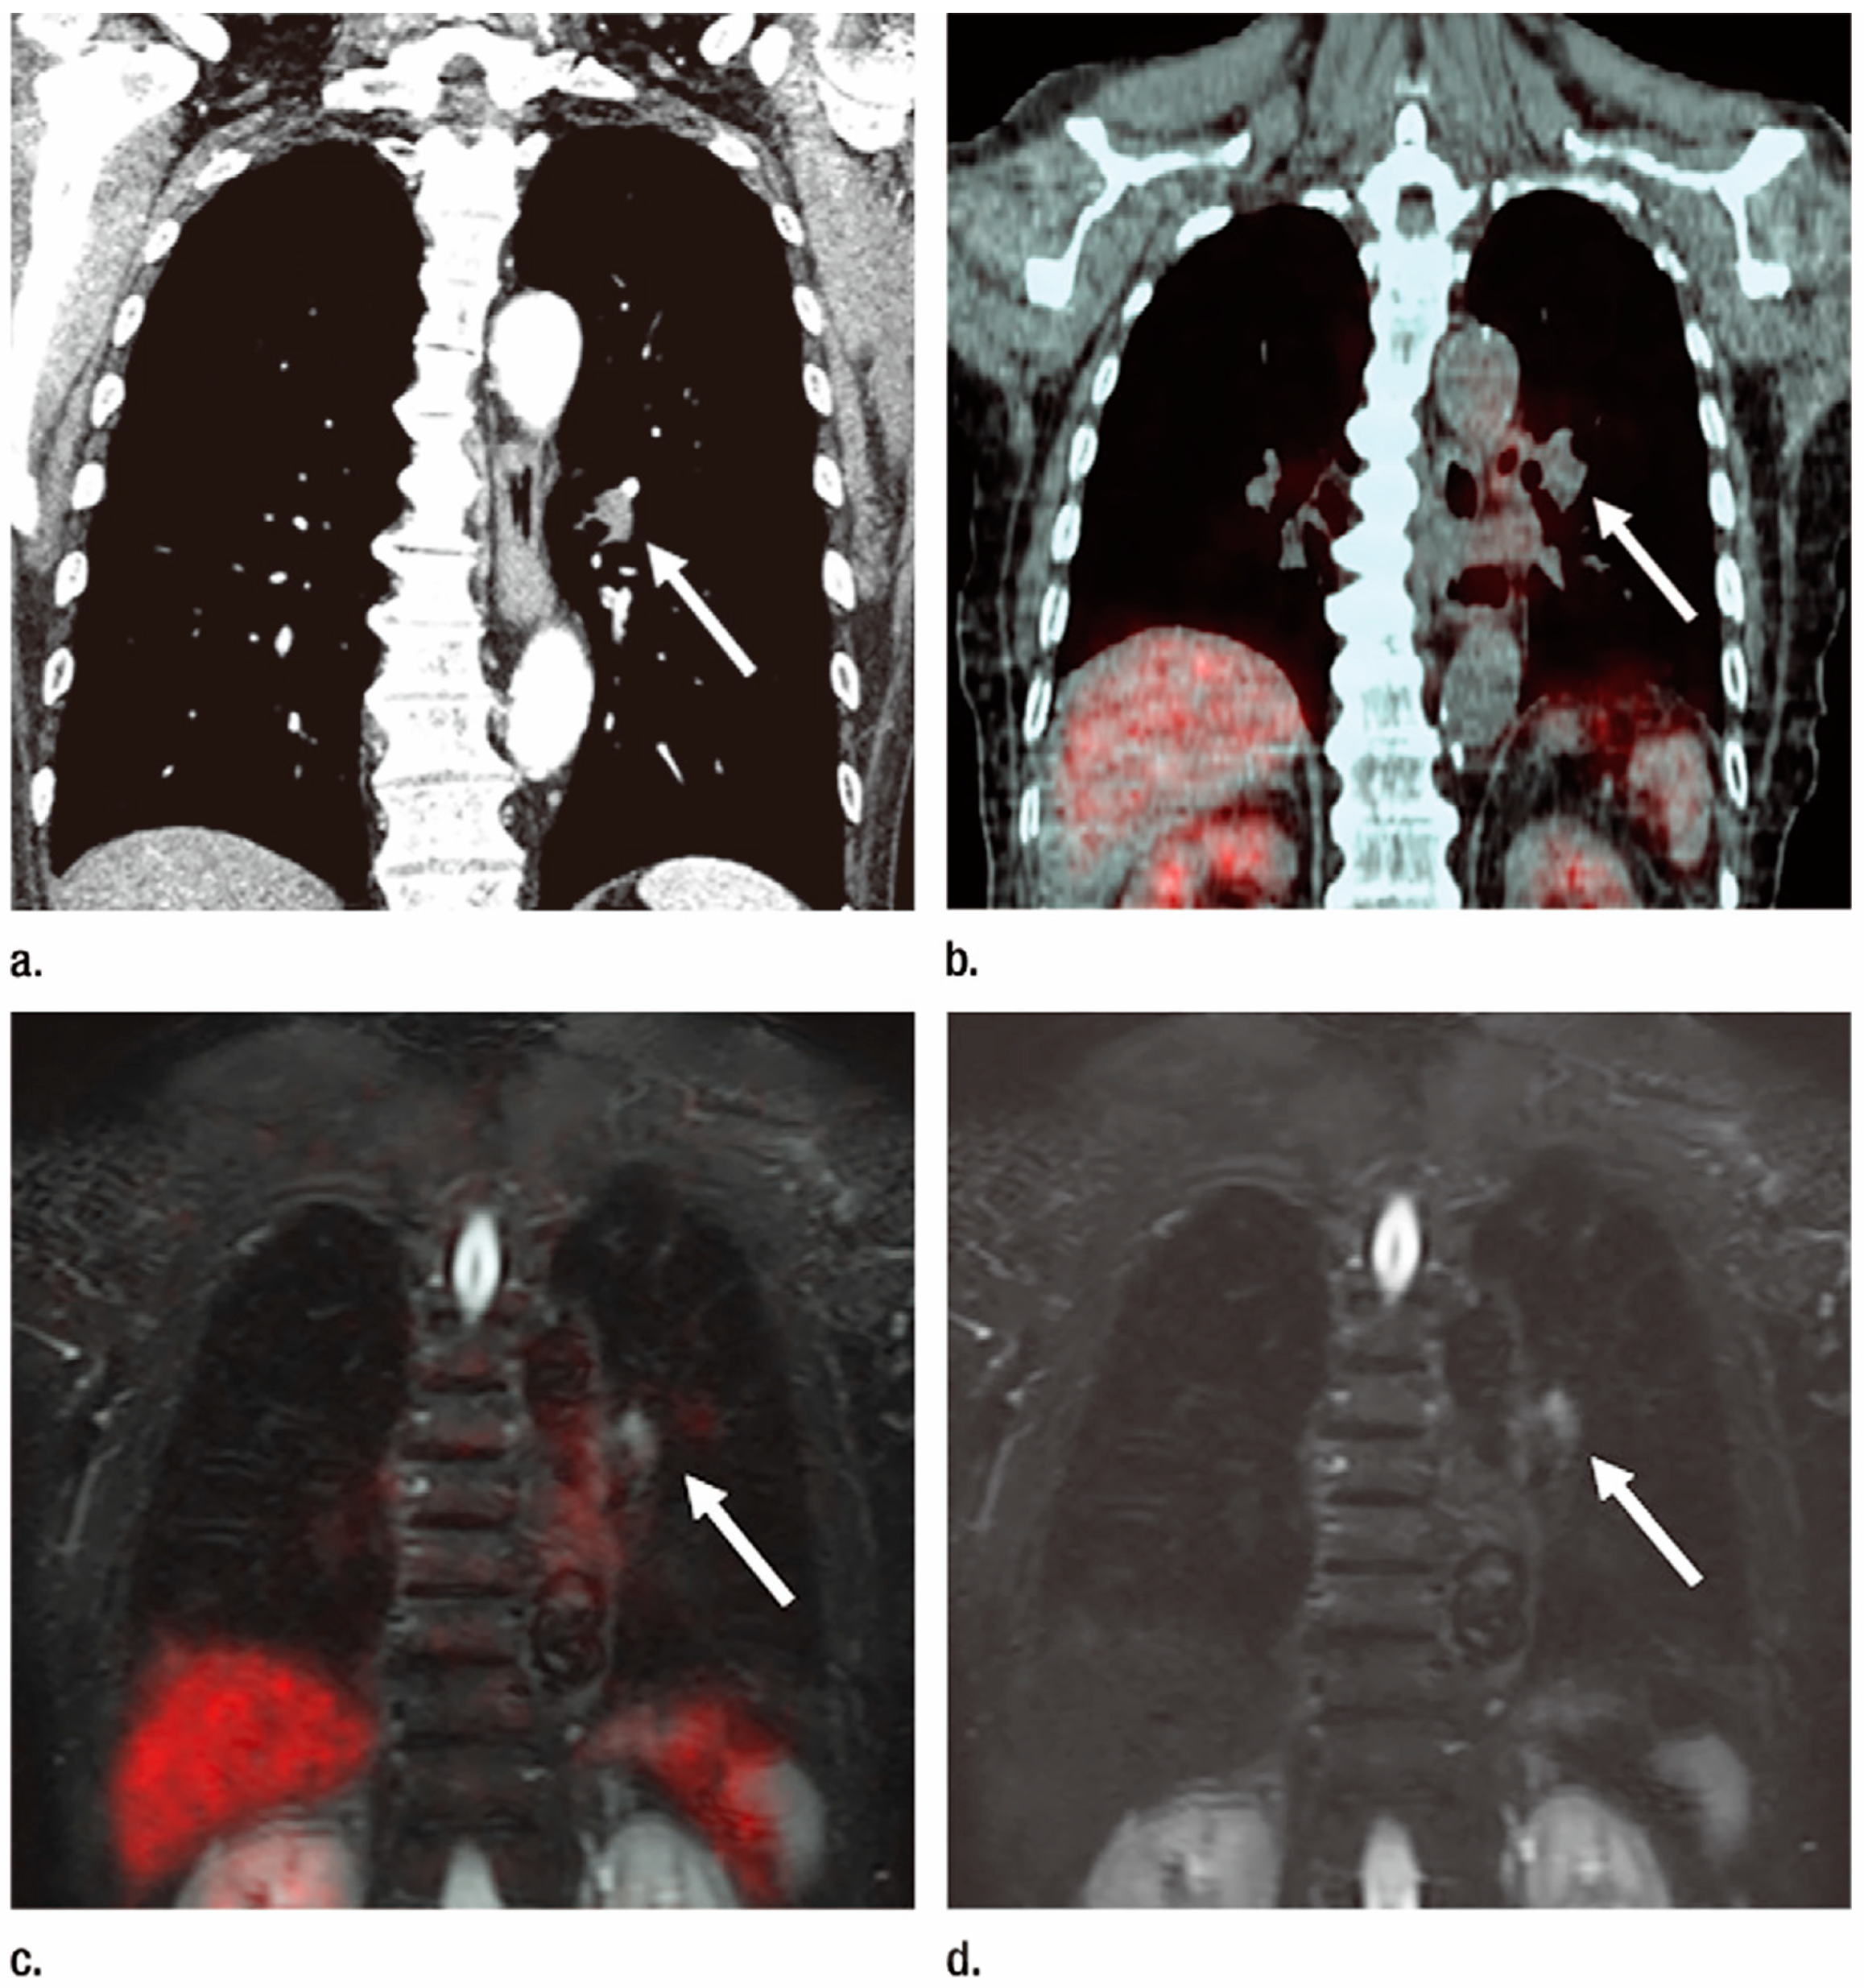

- Ohno, Y.; Koyama, H.; Onishi, Y.; Takenaka, D.; Nogami, M.; Yoshikawa, T.; Matsumoto, S.; Kotani, Y.; Sugimura, K. Non-small cell lung cancer: Whole-body MR examination for M-stage assessment–utility for whole-body diffusion-weighted imaging compared with integrated FDG PET/CT. Radiology 2008, 248, 643–654. [Google Scholar] [CrossRef] [PubMed]

- Takenaka, D.; Ohno, Y.; Matsumoto, K.; Aoyama, N.; Onishi, Y.; Koyama, H.; Nogami, M.; Yoshikawa, T.; Matsumoto, S.; Sugimura, K. Detection of bone metastases in non-small cell lung cancer patients: Comparison of whole-body diffusion-weighted imaging (DWI), whole-body MR imaging without and with DWI, whole-body FDG-PET/CT, and bone scintigraphy. J. Magn. Reson. Imaging 2009, 30, 298–308. [Google Scholar] [CrossRef] [PubMed]

- Ohno, Y.; Nishio, M.; Koyama, H.; Yoshikawa, T.; Matsumoto, S.; Takenaka, D.; Seki, S.; Tsubakimoto, M.; Sugimura, K. Comparison of the utility of whole-body MRI with and without contrast-enhanced Quick 3D and double RF fat suppression techniques, conventional whole-body MRI, PET/CT and conventional examination for assessment of recurrence in NSCLC patients. Eur. J. Radiol. 2013, 82, 2018–2027. [Google Scholar] [CrossRef] [PubMed]